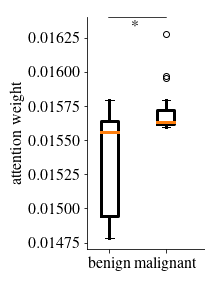

In a first analysis we use the Gleason dataset to create an artificial dataset for which the annotation per image patch is known. Each image in this dataset combines one image showing benign tissue and one image with malignant Gleason grade 5 tissue by stitching half of each together (see example in \figurereffig:fake_attention_example_img). For each image, the attention weights per patch are extracted from the MIL layer of eCaReNet. In the example it can be seen that the upper, malignant part, receives the highest attention weights, while in the benign tissue only relatively bright regions are highlighted. This may be because white regions correspond to glands, which are an important structure to distinguish benign from malignant tissue (see also \figurereffig:apd_att). A boxplot of the attention weights of all 12 example images is shown in \figurereffig:fake_attention_example_box. The attention weights for malignant patches are significantly higher than for benign patches. The original images that were stitched together are neither part of the training nor of the validation or test sets and give an unbiased estimate of importance.

Another experiment was conducted on the survival dataset. From each TMA, one image was randomly chosen from both the validation and test sets of the survival dataset, while maintaining the overall data distribution with respect to the ISUP grades, relapse time and censoring status. An expert pathologist marked tumor regions in each image, enabling us to compare this to the attention weights per patch. A patch is counted as tumorous if 66% of it lie within the marked tumor region. \figurereffig:annotation_example_img shows that all highlighted patches lie within the tumor area, however not all patches in the tumor area receive a high attention weight. \figurereffig:annotation_example_box shows the results on all images showing tumor tissue drawn from the test set. Patches marked as tumor show on average higher attention weights than non-tumor image patches.